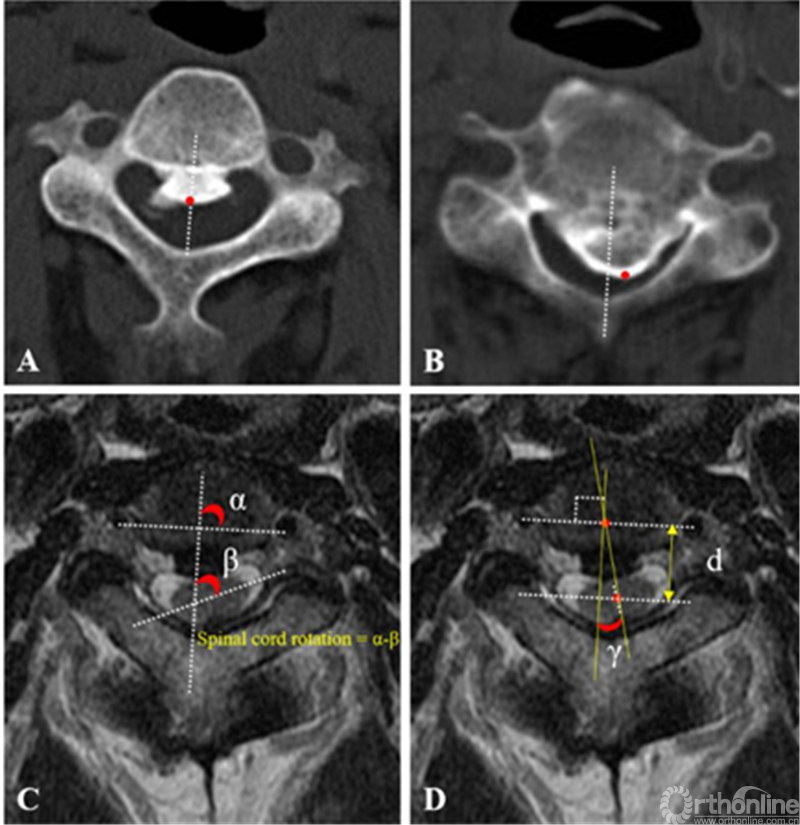

回顾性分析长征医院180例因严重OPLL患者行ACAF(96例)和单侧椎管成形术(84例)的患者资料。测量了脊髓旋转角代表脊髓相对于人体冠状面的位置,脊髓偏移角代表脊髓相对人体矢状面的位置,脊髓距离代表水平面脊髓相对椎体的位置(测量方法如下图)。

测量方法说明:选取MRI上横截面骨化物压迫平面,并取骨化物累及C3/4、C4/5或C5/6层面的角度和距离平均值作为参考指标。通过测量脊髓旋转角、偏移角、位移距离来反应脊髓位置恢复情况。根据Eskander等人基于T2加权成像(T2WI)的轴向平面所述,脊髓旋转角(脊髓相对于椎体的旋转)定义为连接双侧椎动脉(椎动脉线,VAL)的中点的连线与脊髓长轴的连线形成的夹角,(脊髓旋转=α-β,图C)[23]。偏移角定义为连接脊髓短轴中心点和VAL中心点的直线与VAL的中垂线形成的夹角,用黄色虚线表示(图D)。脊髓位移距离定义为脊髓短轴中点与VAL线之间的距离数值,用“d”表示(图D)。